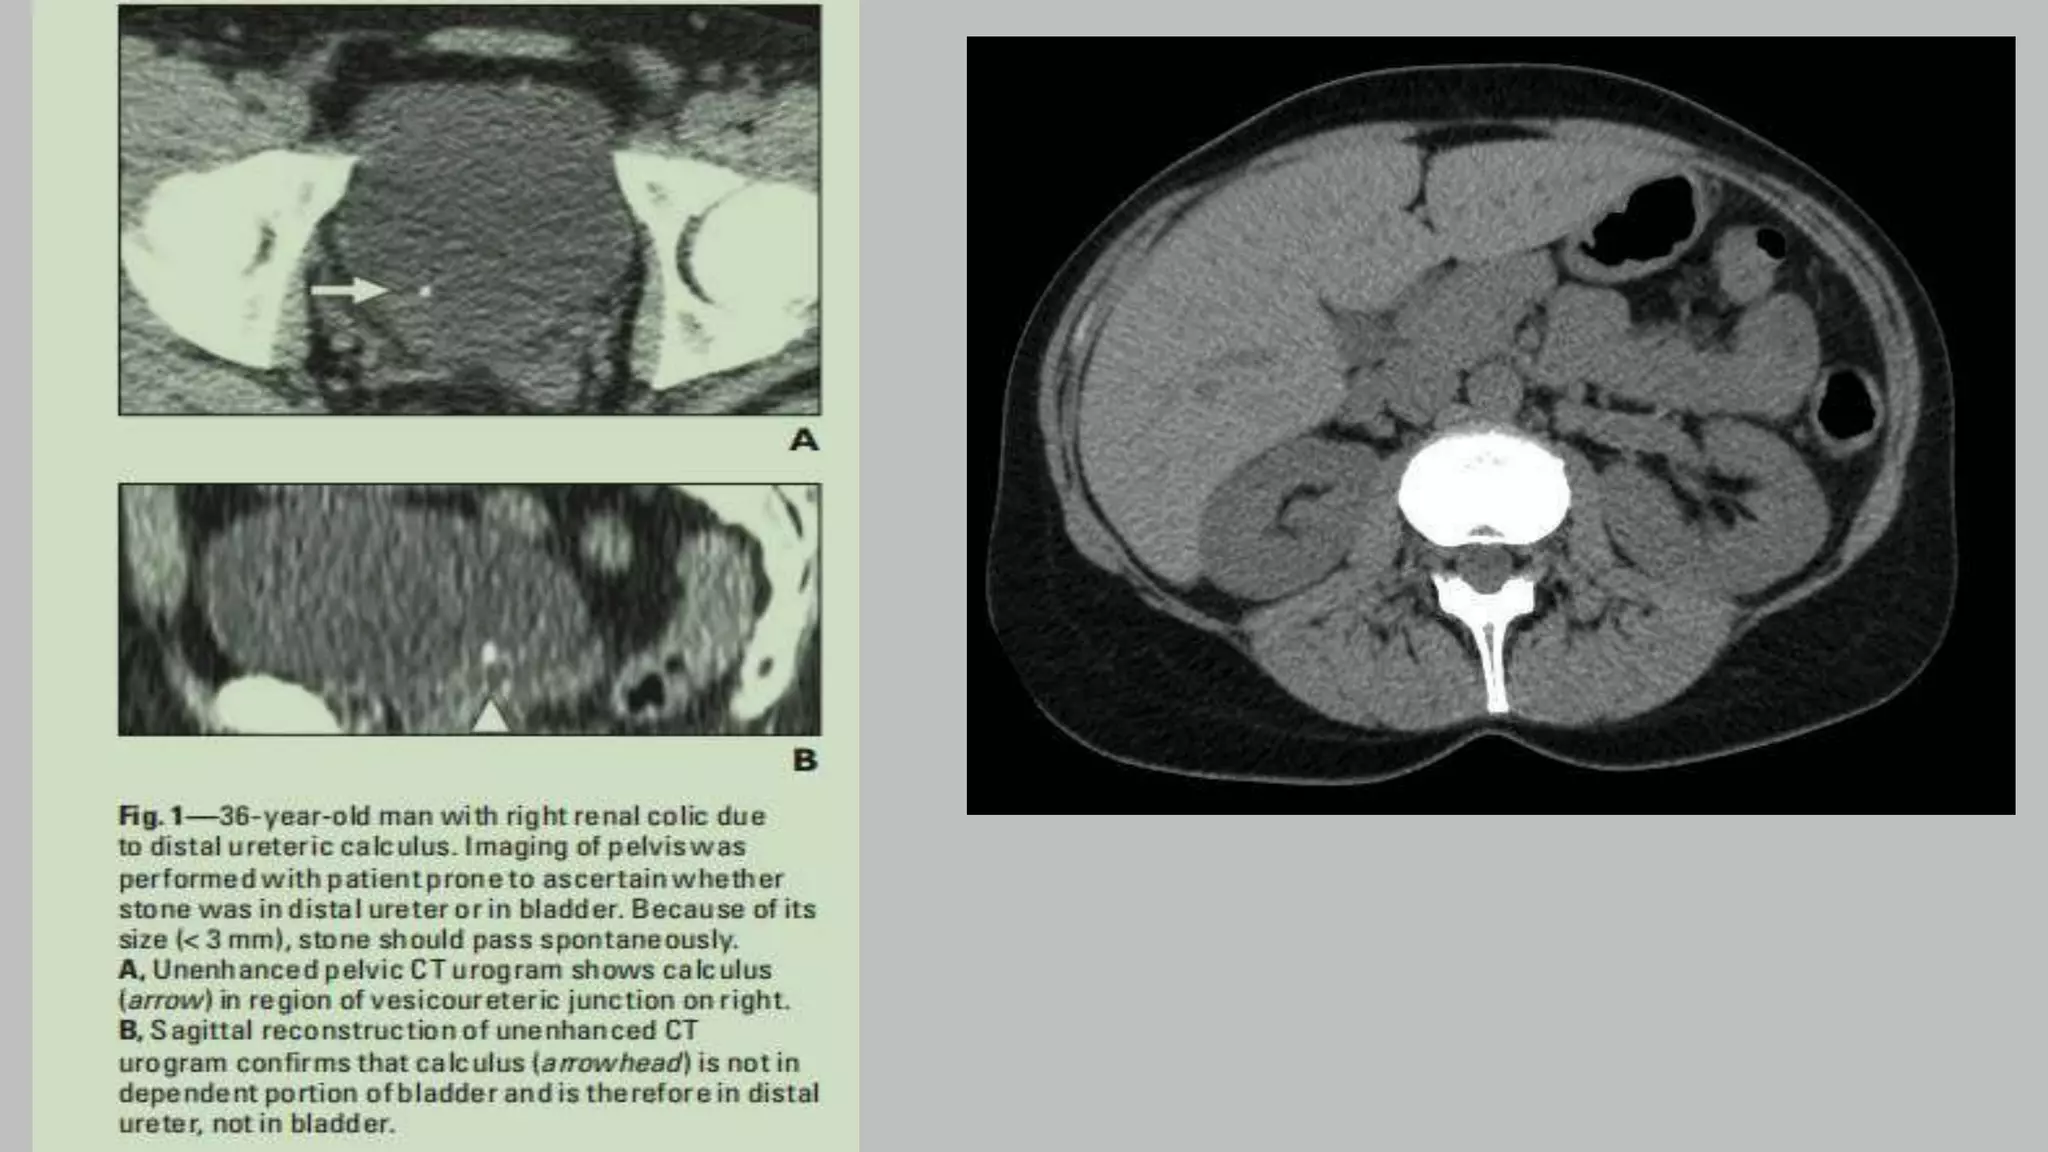

• McNicholas et al (28) showed that excretory phase CT scans obtained with

patients in a prone position also improved opacification of the distal ureters

compared to CT scans obtained in supine patients without abdominal compression.

• Excretory phase axial CT at level of renal hilum.

• CT urogram: Excretory phase obtained 7 minutes following

contrast administration. This phase is used to look for filling

defects in the urinary collecting system.